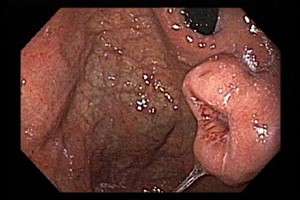

Nội soi: bác sĩ đưa một ống đàn hồi đầu gắn đèn và một máy quay video nhỏ vào cơ thể để xem niêm mạc bên trong của đường tiêu hóa. Tùy thuộc vào vị trí khối u, ống có thể được đưa xuống họng (đối với nội soi trên ) hoặc đưa vào trực tràng (đối với nội soi phía dưới ). Nếu nhìn thấy các vùng bất thường, các mẫu mô nhỏ có thể được lấy ra để sinh thiết (xem bên dưới).

Nội soi cũng có thể được sử dụng để thực hiện cùng siêu âm gọi là siêu âm nội soi (EUS). Siêu âm sử dụng sóng âm thanh để tạo ra hình ảnh bên trong cơ thể. Đối với EUS, một đầu dò siêu âm nhỏ nằm ở cuối ống soi, cho phép nó tiếp cận rất gần khối u. Xét nghiệm này có thể cho biết khối u đã phát triển đến đâu trong thành của đường tiêu hóa. Nó cũng có thể giúp cho biết liệu khối u đã lan đến các hạch bạch huyết gần đó hay chưa.

Hình 3. Hình ảnh nội soi u GIST tại dạ dày

Nguồn: https://www.gastrointestinalatlas.com/english/gastric_gist_.html